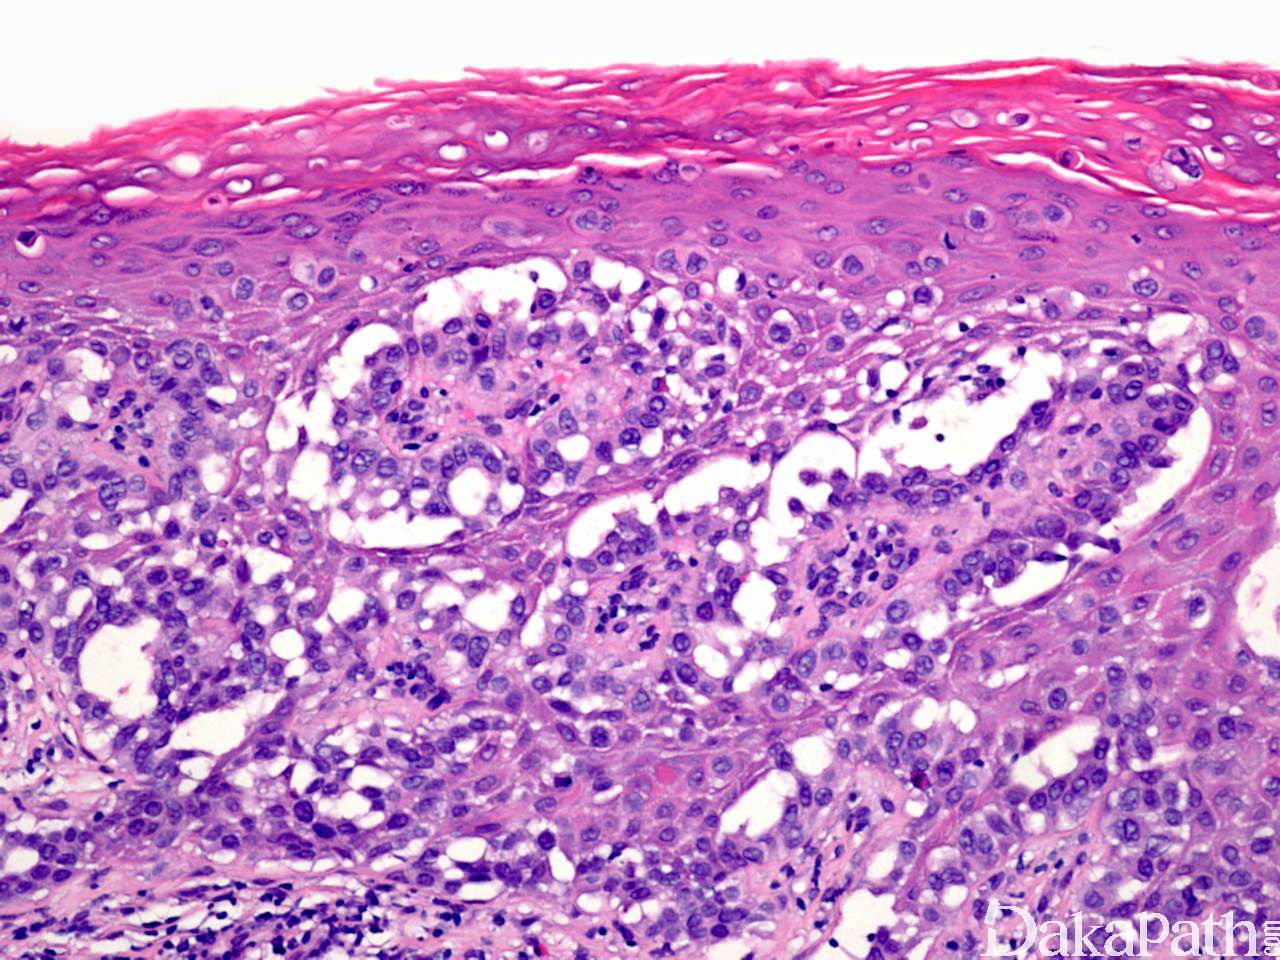

组织学特征性地表现为表皮内非典型上皮细胞单个散在或成群分布于上皮各层内,有时可形成导管或腺样结构;

细胞体积大,胞质淡染、内含黏液或透亮,有时可伴有黑色素颗粒;

Paget 细胞间常见裂隙样结构;

表皮可显著增生。